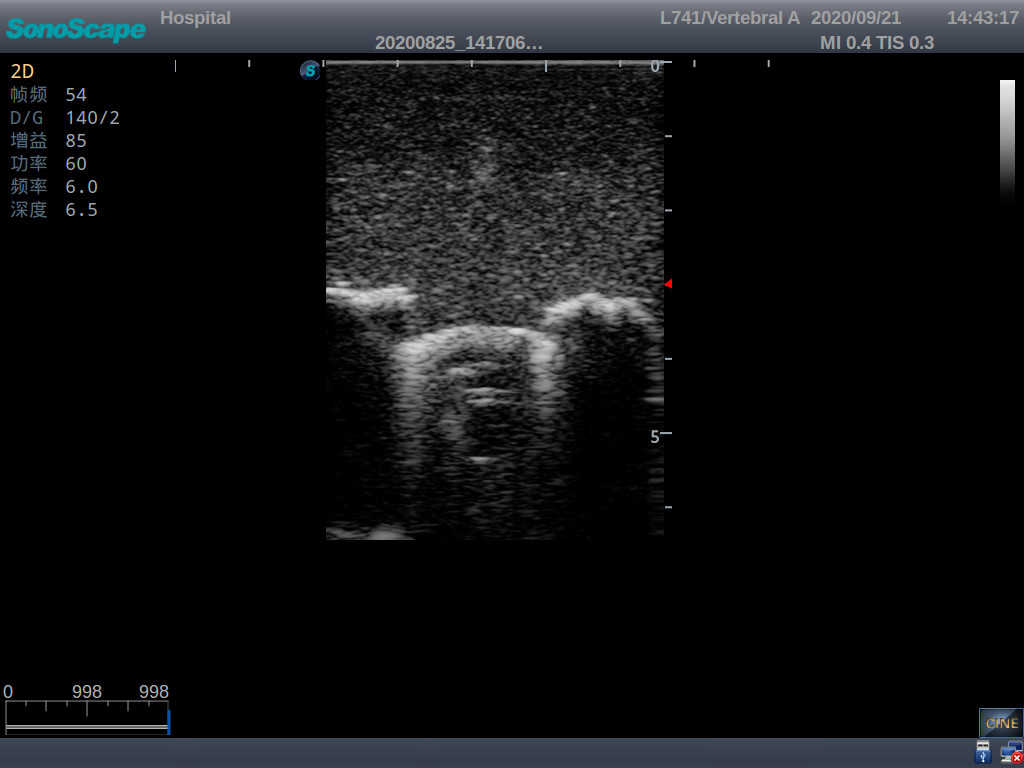

Pediatric Lumbar Puncture Ultrasound Training Model

Model TYE1558.1

This model is an ideal choice for ultrasound-guided pediatric lumbar puncture training with true-to-life skin feel and touch, accurate anatomical structures as well as real clinical ultrasound images. Realistic resistance to needle tips and correct landmarks provide excellent hands-on experience.

Accurate anatomical structure of L1-L5 and the vertebral canal

2)  Real clinical ultrasound images

3)  Compatible with various real ultrasound machines

1)  Ultrasound-guided lumbar puncture practice